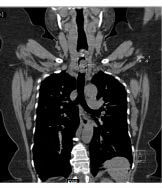

Contrast enhanced computed tomography (CECT) of neck and thorax reported intraluminal mildly enhancing polypoidal mass lesion measuring 2.58 x 1.54 x 1.51 cm (Cc X AP X Tr) in the upper trachea at the level of C6, C7 vertebral body. Significant luminal compromise was noted at the level of the mass lesion. Rest of the lung parenchyma was unremarkable. Flexible bronchoscopy examination revealed a large polyploidal growth approximately 3 cm from the vocal cords. The growth was moving with respiration and causing critical airway narrowing at the upper trachea (approximately 80%).

CECT at presentation: Intraluminal mass lesion in the upper trachea

CECT at presentation